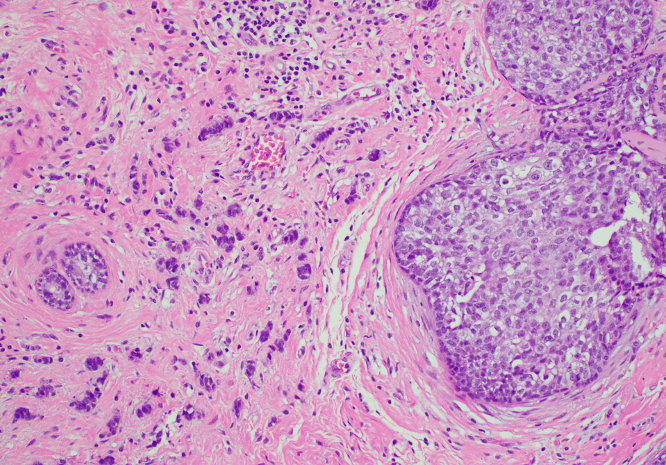

제자리암은 영어로 Carcinoma in situ라고 하며, 말 그대로 ‘제자리에 있는 암’을 의미합니다. 암세포가 생기긴 했지만, 기저막을 뚫지 않아 주변 조직으로 퍼지지 않은 상태를 말합니다. 이 단계에서는 세포가 비정상적으로 변했지만, 혈관이나 림프를 통해 다른 부위로 전이되지는 않습니다.

제자리암과 침윤암의 가장 큰 차이는 ‘퍼짐의 유무’입니다. 제자리암은 세포가 변형되었으나, 그 변화가 한정된 부위에 머무는 상태입니다. 반면 침윤암은 세포가 기저막을 넘어 주변 조직, 림프, 혈관 등으로 퍼진 상태를 말합니다. 따라서 침윤암은 수술, 항암, 방사선 치료 등 적극적 치료가 필요하지만, 제자리암은 비교적 관리 중심으로 접근할 수 있습니다.